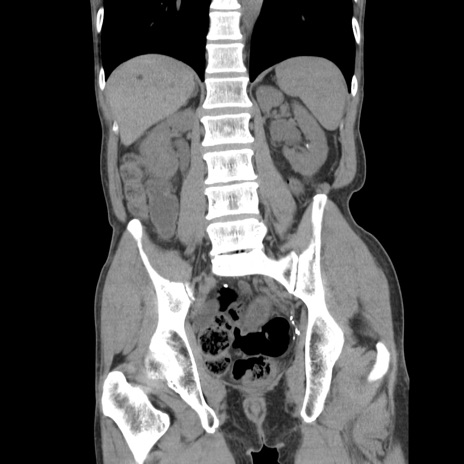

症例11(冠状断像)

【症例】 60歳代男性

【主訴】 下腹部痛

【現病歴】 本日夜中より下腹部痛の症状認め、受診。

【既往歴】 膀胱癌(膀胱全摘+尿管皮膚瘻術) 、胃癌術後

【身体所見】 BT 35.3℃、PR 58/min、BP 136/98mHg、腹部平坦、軟、腸蠕動音±、ストマ留置あり、左上腹部~正中部に圧痛あり、反跳痛なし。

【データ】WBC 5100、CRP0.01